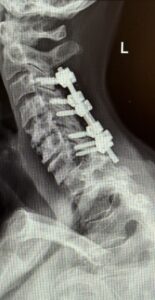

The patient had an uneventful postoperative course with significant improvement in her preoperative symptoms and is now able to maintain a good posture (Fig 2 right).